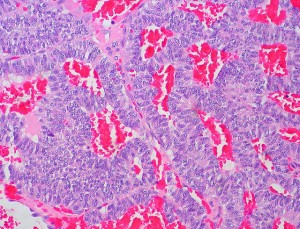

Ahora, un grupo de investigación de la Escuela de Medicina de la Universidad de Yale(2), ha realizado un estudio con ratones en el que han observado que la hormona «quemagrasa» también se produce en unas células especiales de la glándula del timo (órgano especializado del sistema inmunológico) y que aumentando los niveles de producción de esta hormona, aumentaban su esperanza de vida un 40%, debido a que la hormona protegía la pérdida de la función inmune típica del envejecimiento biológico del timo. Cuando esta glándula funciona normalmente, produce nuevas células T para el sistema inmune, pero con la edad, el timo se vuelve graso y pierde su capacidad de producir estas células. Esta pérdida de nuevas células T en el cuerpo es una causa de aumento del riesgo de infecciones y ciertos tipos de cáncer en los procesos de envejecimiento. Los investigadores estudiaron ratones transgénicos que segregaban niveles elevados de la hormona FGF21, encontraron que el aumento de los niveles de FGF21 en ratones de edad avanzada, protegía el timo de la degeneración por grasa relacionada con la edad y por tanto se conseguía alargar el funcionamiento óptimo del timo para producir nuevas células T, mientras que la deficiencia de niveles de FGF21 aceleró la degeneración del timo en ratones mayores.